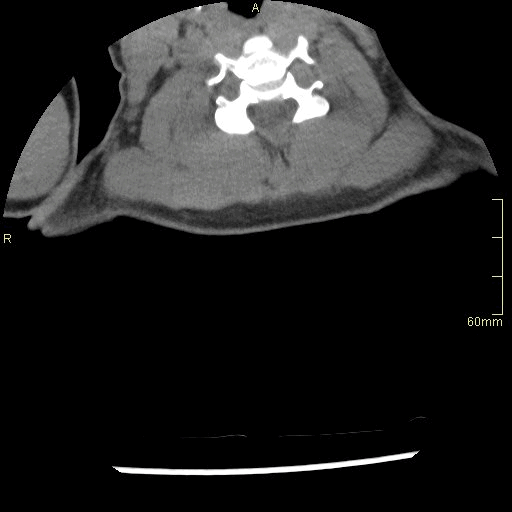

CT Thoracic Spine Non Contrast- Bone window (axial)

CT Thoracic Spine Non Contrast- Soft Tissue window (axial)